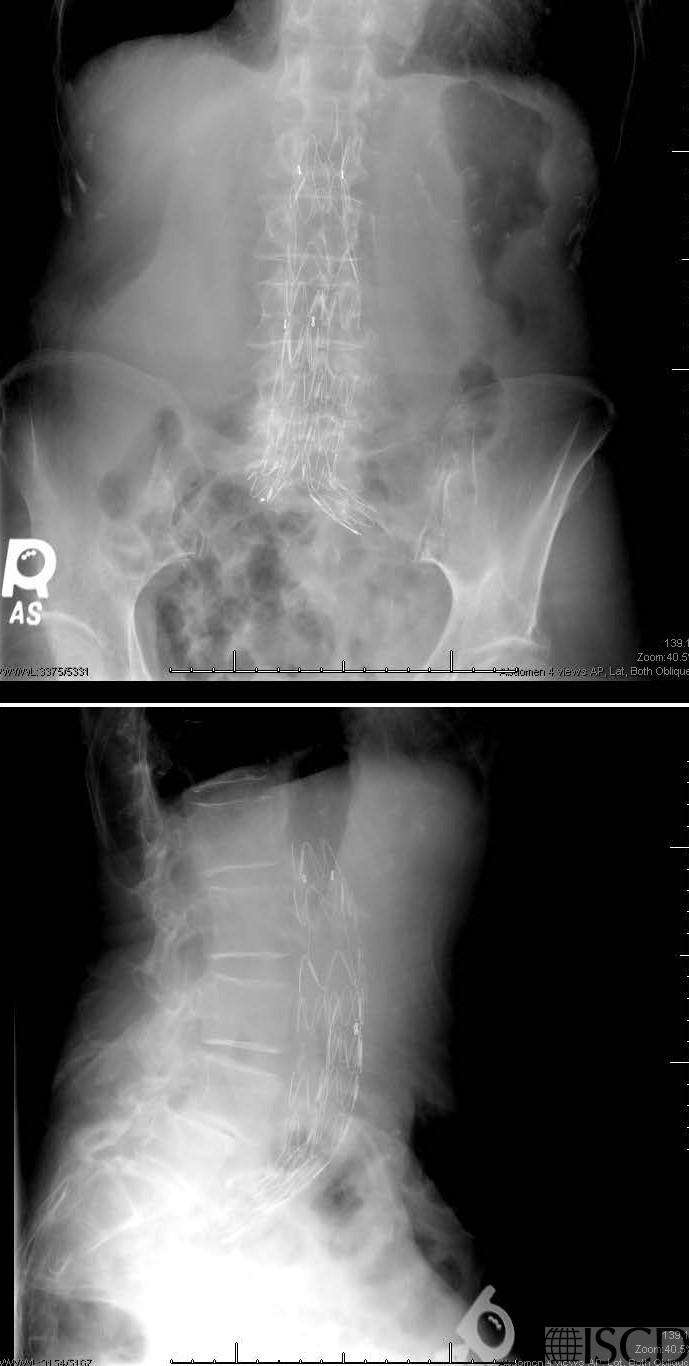

This is the accompany PA and lateral radiograph showing the endograft.

There is a vascular endograft overlying L1-L5. The lumbar spine would not be useful in diagnosis or follow-up.